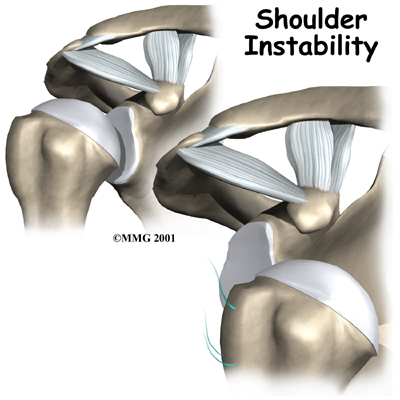

Shoulder instability means that the shoulder joint is too loose and is able to slide around too much in the socket. In some cases, the unstable shoulder actually slips out of the socket. If the shoulder slips completely out of the socket, it has become dislocated. If not treated, instability can lead to arthritis of the shoulder joint.

happen when a force overcomes the strength of the rotator cuff muscles and the ligaments of the shoulder. Nearly all dislocations are anterior dislocations, meaning that the humerus slips out of the front of the glenoid. Only three percent of dislocations are posterior dislocations, or out the back.

Sometimes the shoulder does not come completely out of the socket. It slips only partially out and then returns to its normal position. This is called subluxation.

Shoulder instability often follows an injury that caused the shoulder to dislocate. This initial injury is usually fairly significant, and the shoulder must be reduced. To reduce a shoulder means it must be manually put back into the socket. The shoulder may seem to return to normal, but the joint often remains unstable. The ligaments that hold the shoulder in the socket, along with the labrum (the cartilage rim around the glenoid), may have become stretched or torn. This makes them too loose to keep the shoulder in the socket when it moves in certain positions. An unstable shoulder can result in repeated episodes of dislocation, even during normal activities. Instability can also follow less severe shoulder injuries.

Chronic instability causes several symptoms. Frequent subluxation is one. In subluxation, the shoulder may slip (sublux) in certain positions, and the shoulder may actually feel loose. This commonly happens when the hand is raised above the head, for example while throwing. Subluxation of the shoulder usually causes a quick feeling of pain, like something is slipping or pinching in the shoulder. Over time, you may stop using the shoulder in ways that cause subluxation.

The shoulder may become so loose that it starts to dislocate frequently. This can be a real problem, especially if you can't get it back in the socket and must go to the emergency room every time. A shoulder dislocation is usually very obvious. The injury is very painful, and the shoulder looks abnormal. Any attempted shoulder movements cause extreme pain. A dislocated shoulder can damage the nerves around the shoulder joint.